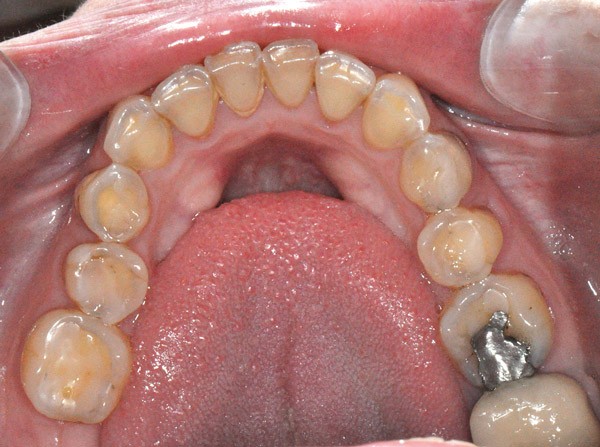

À l’examen clinique (fig. 2 à 4), on observe :

– l’absence de 17, 27 et 47 (suite de lésions carieuses volumineuses) ;

– un parodonte sain ;

– des érosions sévères généralisées, symétriques et bilatérales (occlusales, palatines et vestibulaires au maxillaire) ;

– des lésions carieuses débutantes de site 3 ;

– des obturations préexistantes infiltrées ;

– une vitalité pulpaire conservée sauf au niveau des prémolaires maxillaires ;

– une usure des bords libres des incisives mandibulaires